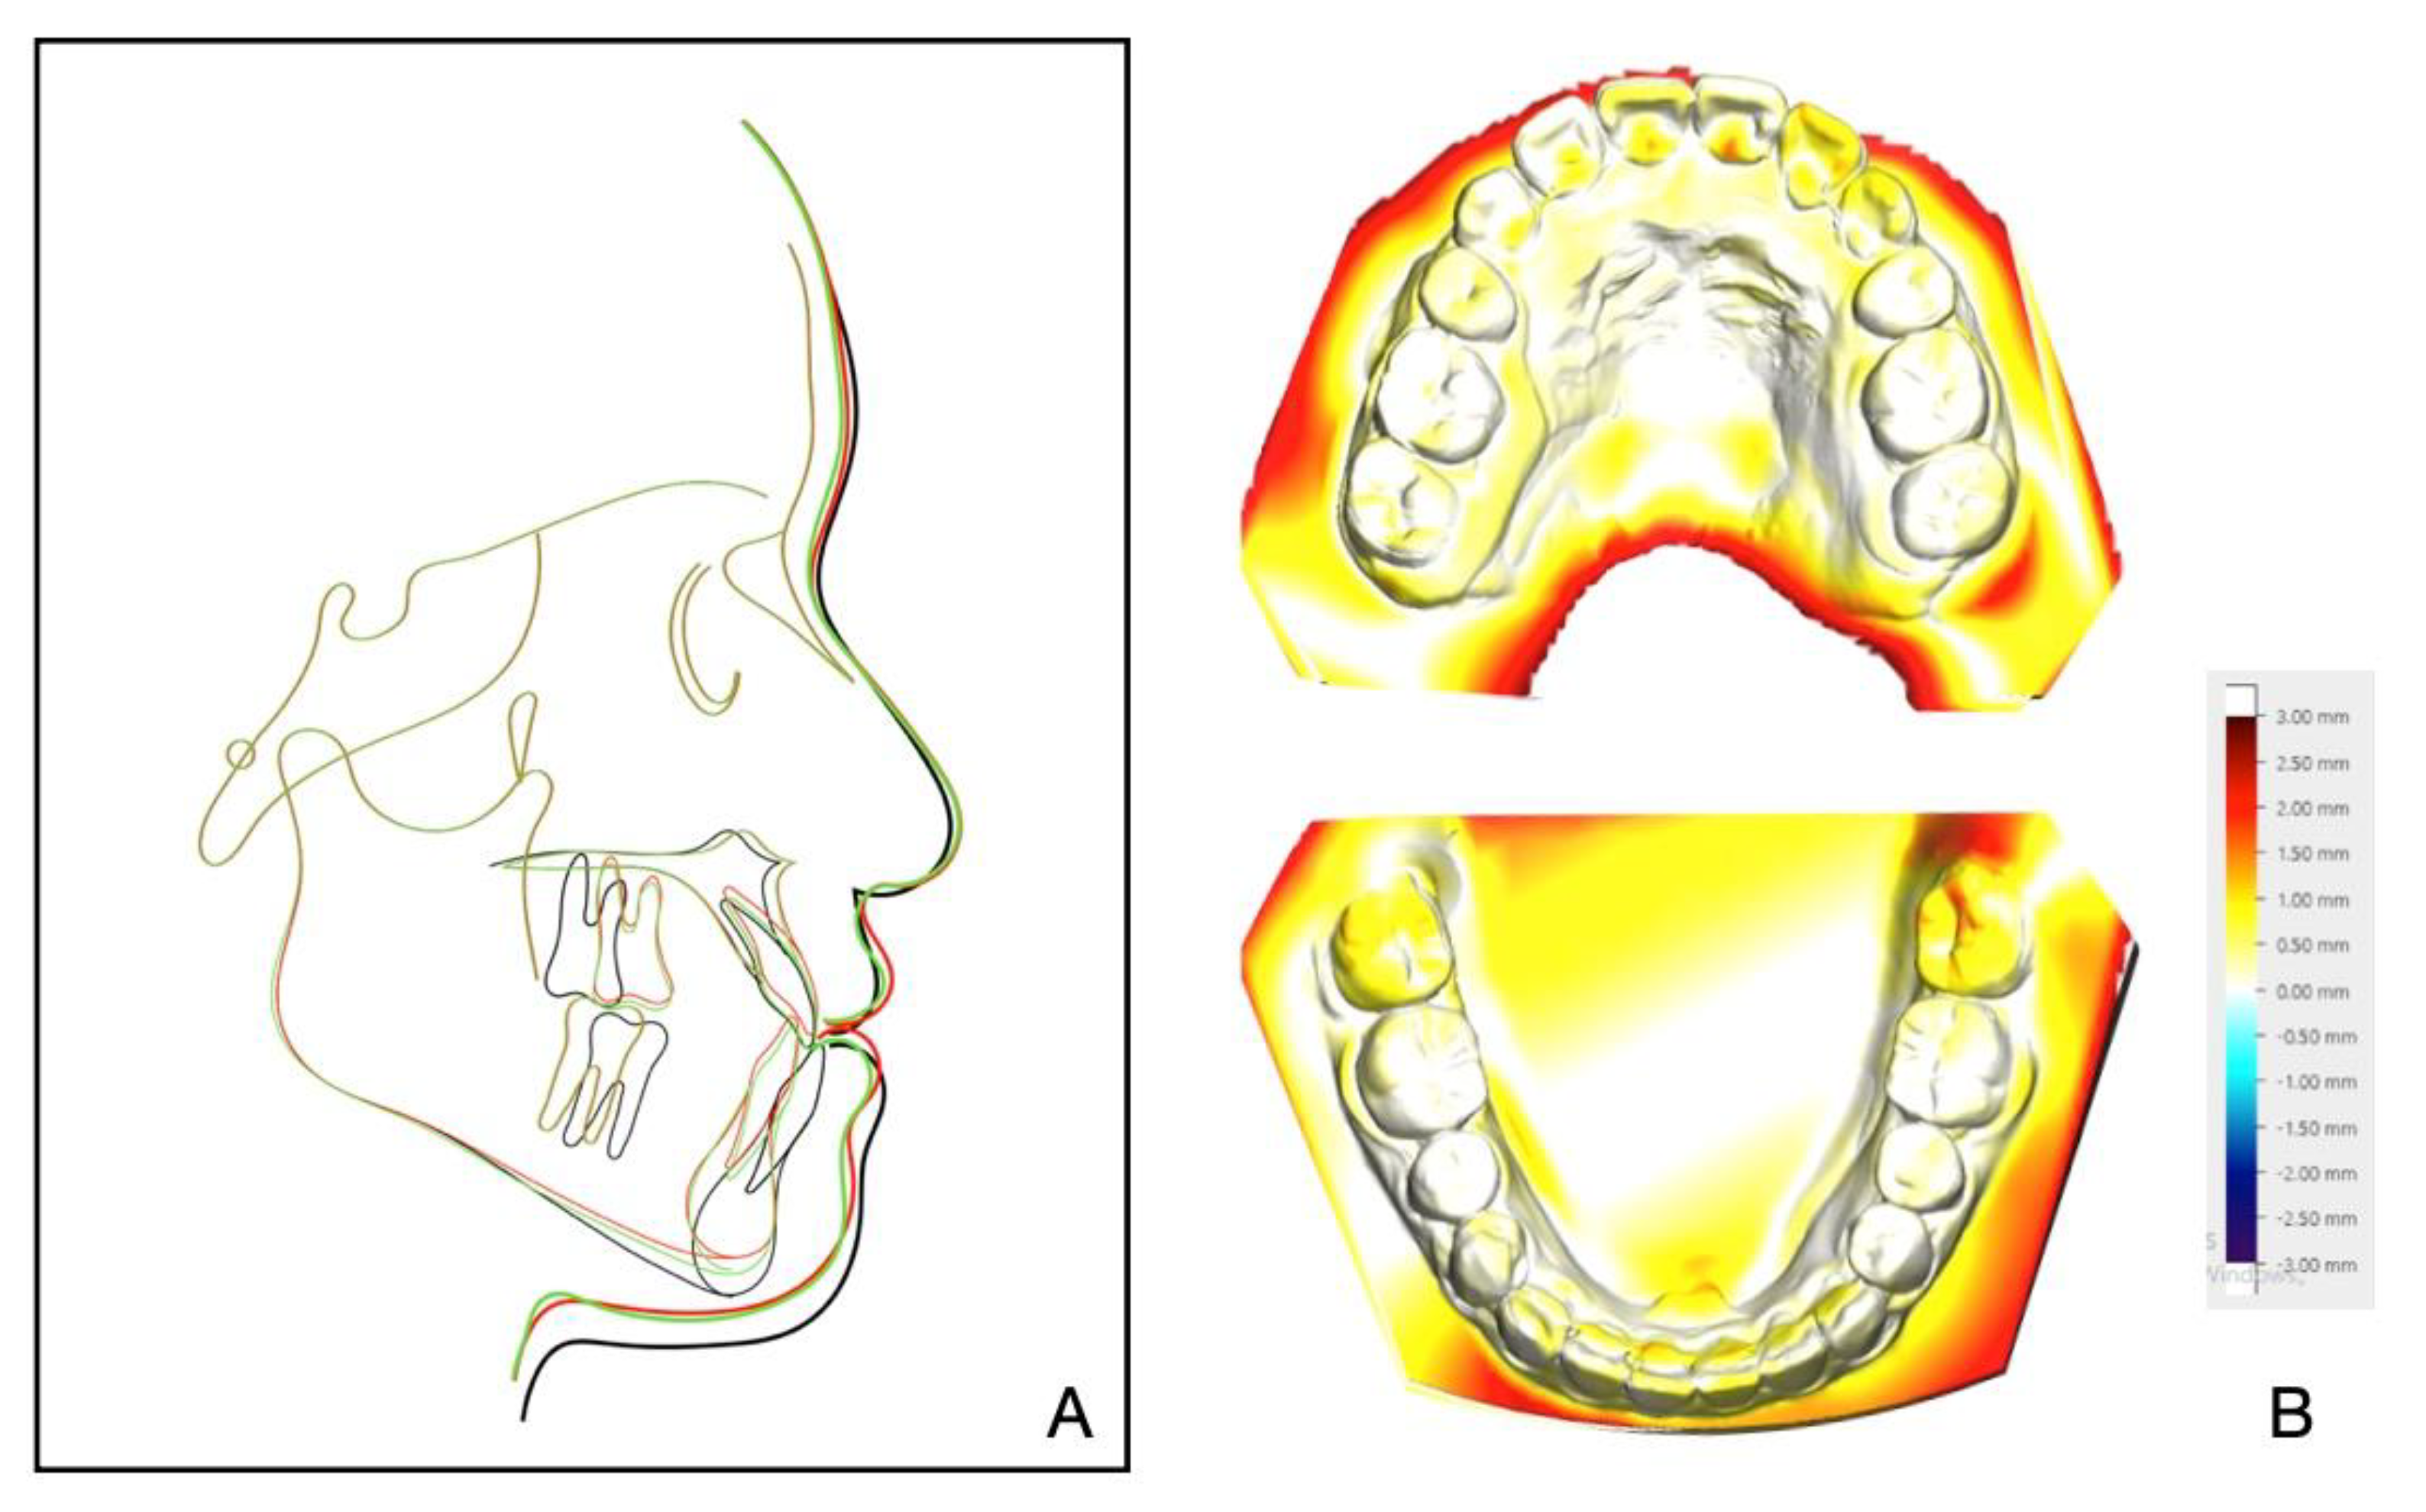

Figure 11. (A) Superimposed cephalometric tracings: pretreatment (black), posttreatment (red), and 8-year follow-up (green). (B) Superimposition of the posttreatment and retention digital dental models.

The 8-year follow-up photographs showed excellent stability of the occlusion and the profile (Figure 10). The pretreatment, posttreatment, and follow-up cephalometric superimposition revealed a significant improvement and stability in the facial profile and the skeletal and dental relationship. Superimposition of the posttreatment and retention digital dental models indicated generally stable results (Figure 11).

Retention and stability following an orthodontic-surgical approach is an important indicator to judge whether a case is successful. The 8-year follow-up showed a stable effect in hard or soft tissues in this case. We applied a rigid internal fixation to settle the jaws during the active orthodontic period, and then we applied a lingual bonded retainer and a Hawley retainer for both arches during the retention period [19]. In addition, the adaptable finishing occlusion and TMJ position were indispensable factors for long-term stability in our case.